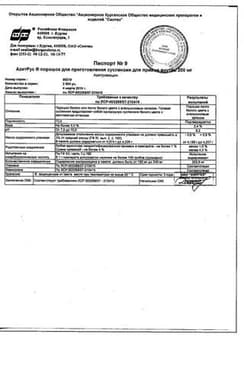

АзитРус порошок для приготовления суспензии для приема внутрь флакон 200 мг пак.4.2 г 3 шт

Инструкция по применению АзитРус порошок для приема внутрь 200 мг пак.4.2 г 3 шт